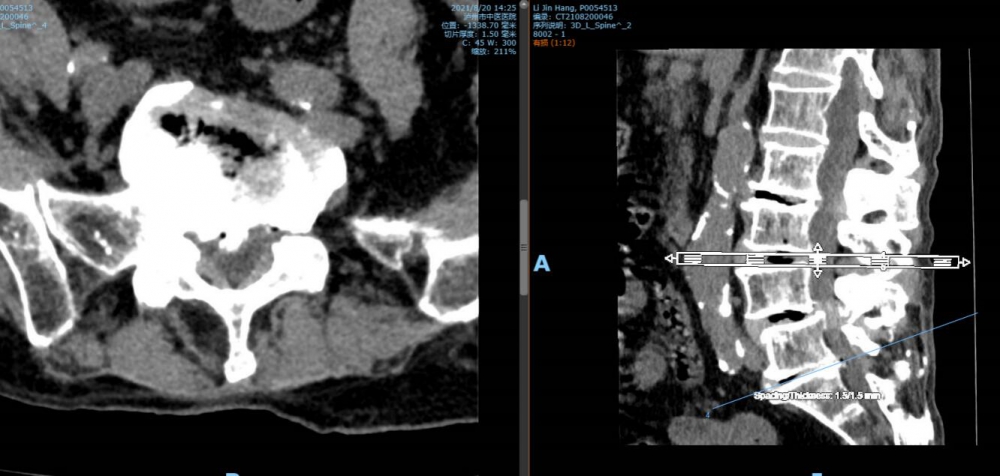

腰5 骶1椎间盘CT

腰5 骶1椎间盘MRI

泸州市中医医院骨伤二科主治中医师胡建超介绍,李谨行老人患有腰椎管狭窄症 、腰4椎I°滑脱 、脊柱退行性侧弯畸形 、冠状动脉粥样硬化性心脏病、心律失常、高血压2级等17种疾病,同时处于慢性阻塞性肺病加重期和脑梗塞恢复期。92岁、全身多种疾病,随时可能会有突发情况,要做这样一个大手术,对医生和患者来说,无疑都是一个巨大的挑战。